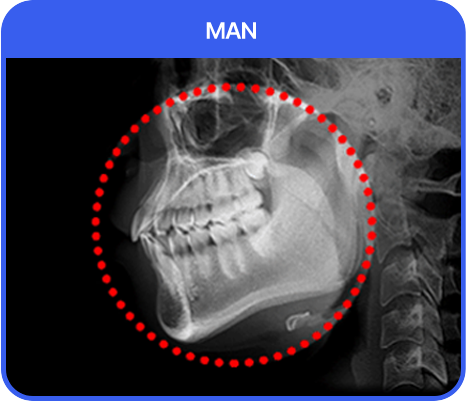

남자 안면윤곽 왜, 아이디일까?

id 남자 사각턱 축소는 id만의 핵심 기술력인 M절골로 정면은

슬림한 선을 만들었고, 측면은 남자다운 각이 살아 있도록 수술합니다.

남자 안면윤곽 수술은 쉬운 수술이 아닙니다. 높은 숙련도와 기술력을 가진

전문의가 있는 아이디에서 멋짐과 안전을 동시에 만족시켜 드리겠습니다.

남자 사각턱 축소 수술 방법

1. id-M 절골 수술법 id-M 절골 수술법